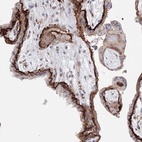

Immunohistochemical staining of human placenta shows strong membranous positivity.